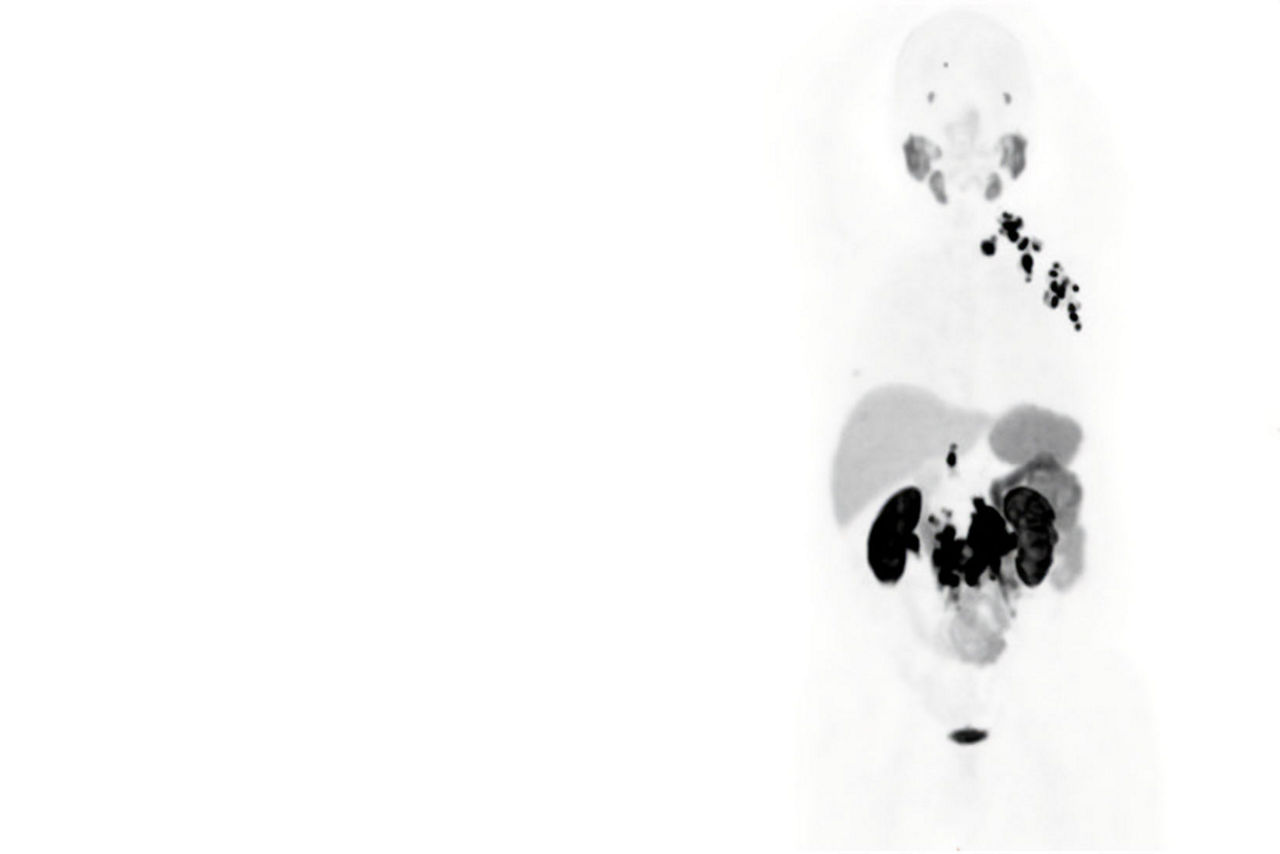

Seen here is a theranostics 18F-PSMA case, after prostate removal. There was suspected recurrence due to elevated markers. No pathological findings at the surgery area.

This image is a theranostics 68Ga-PSMA case for prostate cancer assessment response to treatment. There were pathological findings in the lymph nodes in the pelvic area.

Omni Legend is built with innovative capabilities to make it an industry-leading PET/CT platform, enabling exemplary diagnostic confidence for your team now and in the future. We designed Omni Legend with theranostics in mind by utilizing ultra-high sensitivity, high resolution, Q.Clear and MotionFree to help personalize dose as well as imaging 68Ga for diagnosis, staging or restaging. The first-of-its-kind Omni Digital Detector and Precision DL are designed to reach new levels of sensitivity and detectability for incredibly clear images. And the brand-new Omni platform gives you exceptional control over the future of your PET/CT capability going forward.